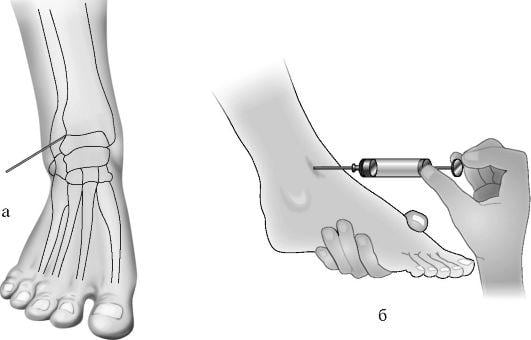

Пункцией извлекается экссудат для биохимического исследования. Биологические образцы также помещаются в питательные среды. По сформировавшимся колониям можно определить видовую принадлежность возбудителей, их чувствительность к лекарственным средствам, степень тяжести тендовагинита голеностопа.

У пациентов с тендовагинитами высокой степени тяжести нередко возникают боли, не устраняемые даже парентеральным введением НПВС. В таких случаях проводятся медикаментозные периартикулярные блокады с анестетиками (Новокаин, Лидокаин) и глюкокортикостероидами (Гидрокортизон, Дексаметазон, Триамцинолон). Из-за выраженных побочных проявлений гормональные препараты не используются дольше 2-3 дней.